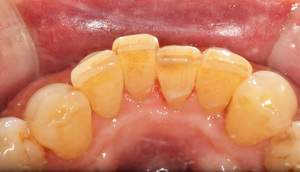

歯石除去

治療前

治療後

| 年齢 | 25歳・男性 |

| 主訴 | 歯石をとりたい・検診 |

| 治療内容 | 各種検査・歯石除去 |

| 治療期間 | 60分 |

| 費用 | 初診料3,000〜4,000円前後 +歯石除去約1,000円 |

| リスク・副作用 | ・処置後に歯がしみることがあります。 ・歯と歯の間に隙間ができるので、息が漏れ発音しにくいと感じることがあります。 ・歯ぐきの炎症が軽減すると歯ぐきが引き締まり、歯が長く見えることがあります。 |

| 担当者所見 | 前歯の裏側にすぐに歯石が溜まってしまいザラザラして気になるとご相談いただいたので適切な歯ブラシの当て方とフロスの通し方をお伝えさせて頂きました。 |